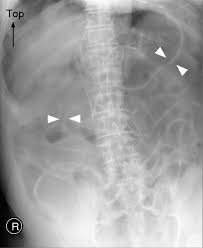

Rigler Sign

See the outline of the small and large bowel outlines - outlined by intraperitonial gas

Free air - Best seen in the right upper quadrant